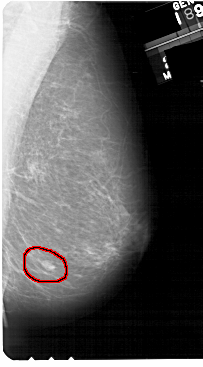

A_1426_1.LEFT_MLO

LEFT_MLO LINES 5491 PIXELS_PER_LINE 3181 BITS_PER_PIXEL 12 RESOLUTION 43.5 NON_OVERLAY

FILE: A_1426_1.RIGHT_MLO.OVERLAY

TOTAL_ABNORMALITIES 1

ABNORMALITY 1

LESION_TYPE MASS SHAPE OVAL MARGINS ILL_DEFINED

ASSESSMENT 4

SUBTLETY 4

PATHOLOGY BENIGN

TOTAL_OUTLINES 1

BOUNDARY